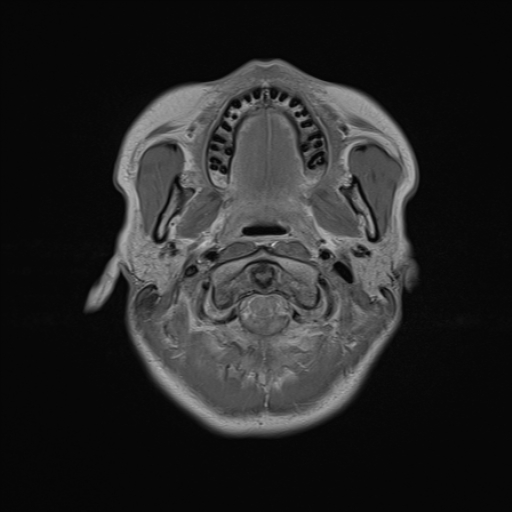

Esame: RM ENCEFALO MDC del 24-03-2026

Descrizione Serie: t1_se_tra

Modalità: MR